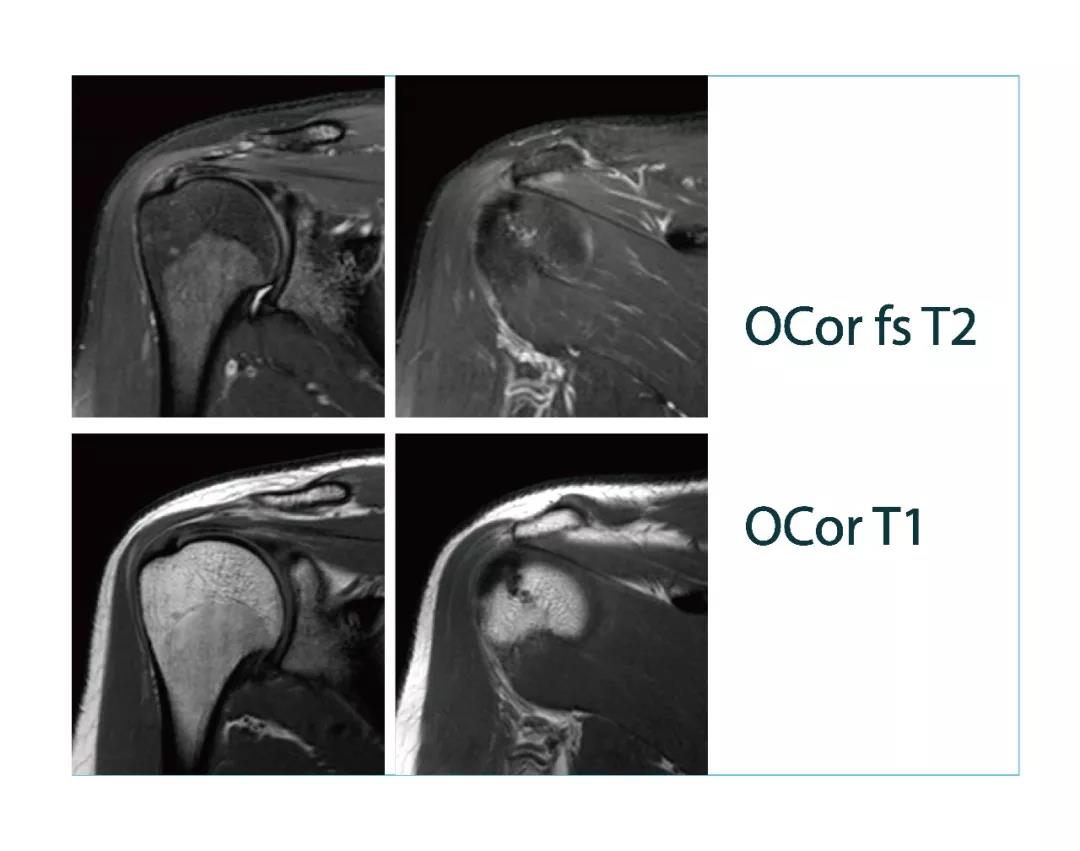

【朗润影像档案】磁共振影像病例分享(编号20180323)

【朗润影像档案】20180323磁共振影像病例结果讨论